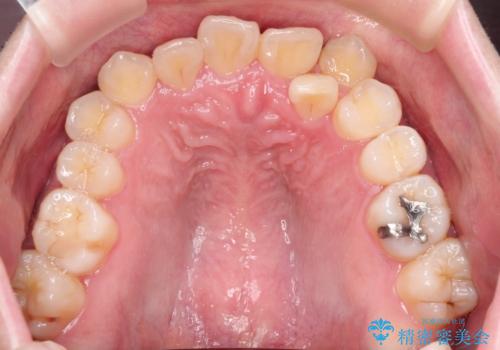

【重度叢生ワイヤー矯正】きれいな歯並びにしたい

- きれいな歯並びにしたいとの希望を持って来院された患者様です。

上下左右小臼歯を抜歯する治療計画を立て審美装置にて治療を行いました。

骨格的3級傾向もあり、咬合関係を仕上げるのに時間がかかりましたが、患者様には大変満足していただけました。

難しいケースでしたが、矯正用アンカースクリューを用いながら、臼歯関係もきれいに仕上げることができました。